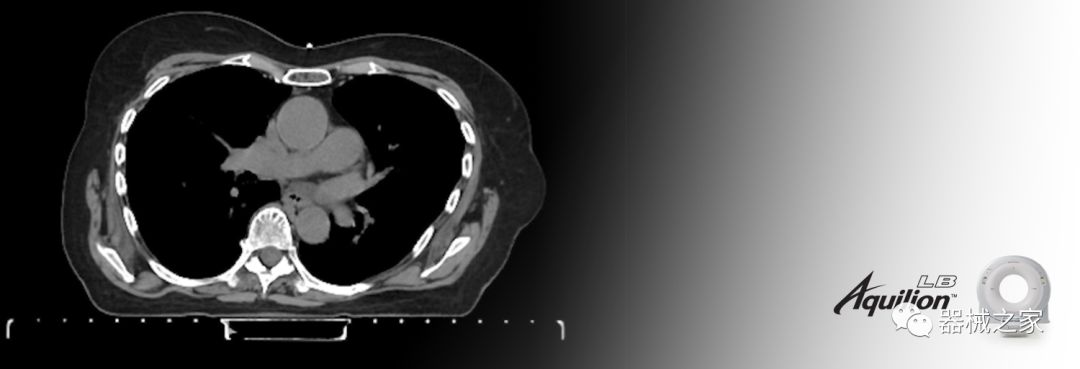

在以患者為中心的放射腫瘤學(xué)領(lǐng)域,計算機斷層掃描(CT)的可訪問性,可重復(fù)性和靈活性至關(guān)重要。為了建立這些價值,佳能醫(yī)療系統(tǒng)美國公司現(xiàn)在正在擴大其放射腫瘤學(xué)CT模擬產(chǎn)品,包括Aquilion Prime SP和Aquilion Lightning 80高級CT系統(tǒng)。除了Aquilion LB之外,Aquilion Prime SP和Aquilion Lightning 80現(xiàn)在還包括放射治療(RT)選項,可為腫瘤學(xué)規(guī)劃提供高質(zhì)量的CT成像和精密工具。

擴展視野(EFOV)可以看到更多的解剖結(jié)構(gòu)。Aquilion LB采用85 cm EFOV,而Aquilion Prime SP和Aquilion Lightning 70采用70 cm EFOV。

佳能醫(yī)療的Aquilion Lightning 80掃描儀還以緊湊,經(jīng)濟的包裝提供高質(zhì)量的成像。Aquilion Lightning 80旨在可靠,高效地運行,在繁忙的環(huán)境中生成高質(zhì)量的圖像。

兩個CT系統(tǒng)均采用0.5 mm x 80排PUREViSION探測器技術(shù)(可配置并從80-160現(xiàn)場升級),78 cm孔徑,50 cm視野,AIDR(自適應(yīng)迭代劑量減少)3-D和SEMAR(單個)能量金屬神器減少)技術(shù)。

Aquilion LB專為滿足腫瘤學(xué)挑戰(zhàn)而設(shè)計,同時優(yōu)先考慮患者護理。Aquilion LB的內(nèi)徑為90 cm,能夠幫助復(fù)雜的患者設(shè)置并提高患者的舒適度。CT模擬定位可以輕松鏡像放射治療定位,更加自信。該系統(tǒng)采用0.5 mm x 16排(32層)PUREViSION探測器技術(shù),70 cm視野,AIDR 3D和SEMAR技術(shù)。